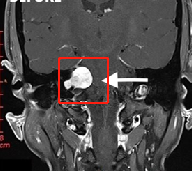

复发性较大听神经瘤手术全切案例:较大听神经瘤手术治疗具挑战性,因为此类患者通常表现为多发性颅神经缺损和脑干受压或颅内高压症状。治疗岩骨严...

MRI的发展和普及增加了小的听觉的神经瘤(ANs)检测的几率。目前,小型听神经瘤的3种治疗方案分别是影像随访观察(等待扫描)、放射外科和/或肿瘤切除。通...